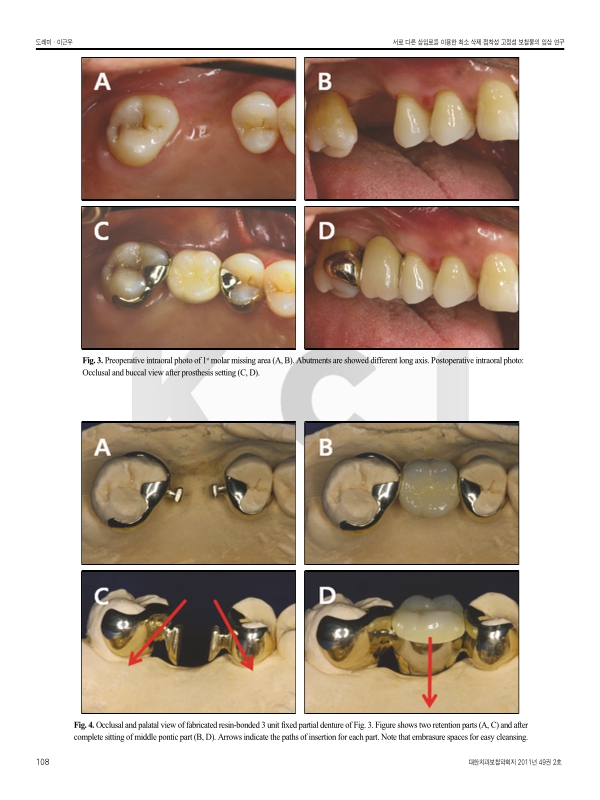

Purpose: The object of this clinical study was to evaluate the short-term outcome of modified resin-bonded fixed partial dentures which utilizes the original tooth undercuts and different path of insertion of components.

Materials and methods: 71 units of modified RBFPDs that were used in 21 patients at the Department of Prosthodontics, College of Dentistry, Yonsei University were evaluated. The follow-up period was up to 25 months, the mean being 7 months. Survival rate, mobility, percussion, probing depth, bleeding on probing, plaque index was recorded and radiographs were taken to monitor alveolar bone loss.

Results & Conclusion: Within the limits of this short term retrospective study, it was concluded that: 1. No mechanical failure such as debonding or fracture of the framework was found during the follow-up period. 2. The periodontal apparatus was stable and no clinical change was observed after prosthetic treatment. 3. No significant marginal bone loss was found in the radiographic evaluation.기사명 | 저자명 | 페이지 | 원문 | 목차 |